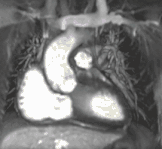

Atrial septal defect with dilation of the right ventricle by CMR